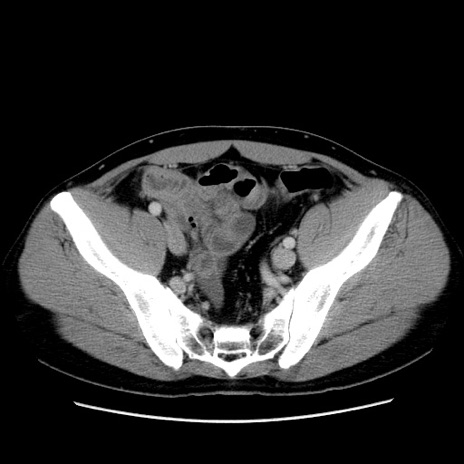

冠状断像

【症例】30歳代男性

【主訴】腹痛、嘔吐

【現病歴】昨晩から突然の腹痛あり、その後嘔吐、軟便も出現。腹痛が改善しないため救急搬送となる。2日前にしめ鯖の食事歴あり。

【身体所見】意識清明、苦悶様、BP 135/90mmHg、BT 35.7℃、腹部:平坦、やや硬、心窩部〜臍部に自発痛、圧痛あり、筋性防御+、反跳痛-

【データ】WBC 8100、CRP 0.57